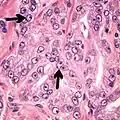

- Relatively common and highly specific

- [4]

- Multiple nucleoli

- Eccentric nucleoli[4]

-

Acinar adenocarcinoma with multiple nucleoli. -

Acinar adenocarcinoma with double and eccentric nucleoli.